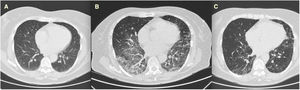

We present the case of a 72-year-old woman with RA since 1997 treated with 25mg of methotrexate (MTX) weekly and 125mg of abatacept weekly, in remission. In 2018 she complained of a dry cough and was studied with CT scan (normal, Fig. 1A), and finally diagnosed with gastric reflux.

In September 2020, one month after hospital discharge, she was still reporting stable dyspnea on moderate efforts, the CT scan was as shown in Fig. 1B (ground glass areas and thickening of interlobular septa in both lower lobes, patchy ground consolidation in all lobes, and honeycomb changes in the left upper lobe), and the functional tests were as follows: FEV1 2140ml (104% of predicted value), FVC 2620ml (99%), DLco (corrected for hemoglobin) 3030mmol/kPa/min (49%). She was treated by pneumologists with a descending dose of 0.5mg/kg of prednisone for a month. Six months later functional tests improved – FEV1 2240ml (111%), FVC 2740ml (105%), DLco 3950mmol/kPa/min (64%) – as well as the CT scan (Fig. 1C). To date, she has not reported dyspnea and her baseline saturation is 99%. She has maintained MTX and abatacept without any adverse event or RA flare. NSAIDs or other corticosteroids have not been needed.